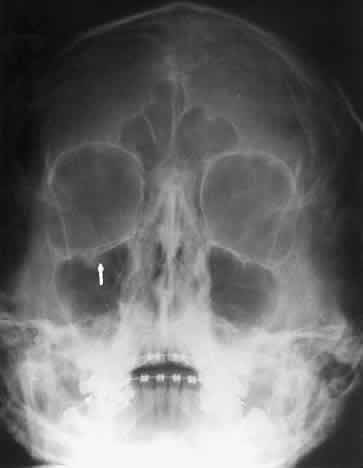

The posterior segment of the lateral wall courses posterior medially and can be seen in anterior projections such as the Caldwell view. This view allows direct visualization of the greater sphenoid wing contribution to the lateral wall. Bone density changes in the greater wing of the sphenoid, such as from a meningioma, can be detected. Fractures of the lateral orbital wall can occur from blunt trauma to the malar prominence. The zygomatic complex fracture (tripod) results from separation of the zygomatic-frontal, zygomatic-temporal, and the zygomatic-maxillary sutures. These fractures are associated with an inferior displacement of the malar prominence and a rounded lateral canthus (Figs. 8 and 9).

Fig. 8. A zygomatic complex fracture (tripod) after blunt trauma to the right cheek. Note the right zygoma is inferiorly displaced. (a, zygomatic-frontal suture separation; b, orbital rim disruption; c, opacification of maxillary sinus)

Fig. 9. Bilateral zygomatic complex and LeFort II fracture after reduction using fixation plates. Caldwell projection shows good alignment of orbital margin and zygomatic bones.